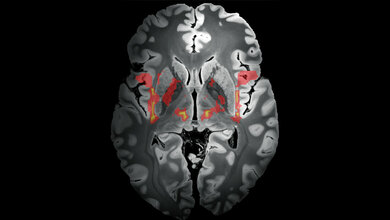

Zu den Erkrankungsursachen von Tic-Störungen ist nur wenig bekannt. Es wird angenommen, dass sowohl genetische als auch Umweltfaktoren, die die Regulationssysteme (zum Beispiel das Immun- und das endokrine System) beeinflussen, zusammenwirken könnten, um eine neurobiologische Anfälligkeit für die Entwicklung von Tics zu schaffen.